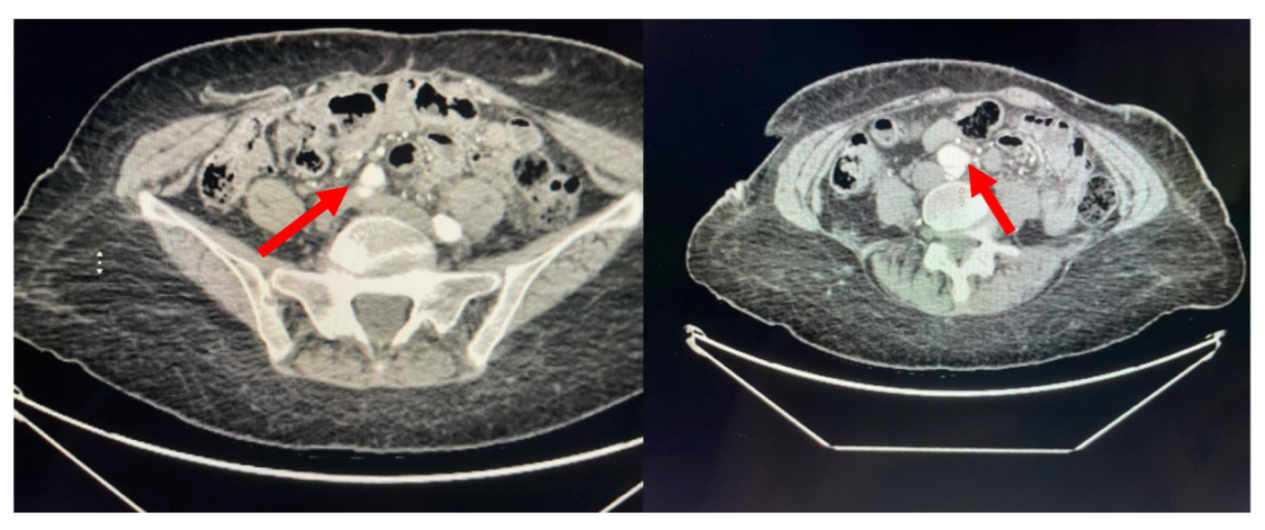

A 71-year-old African American female with a past medical history significant for chronic, benign hypertension well controlled on metoprolol succinate 25 mg once a day presented to our practice in 2014 for a cardiac evaluation. Her index transthoracic echocardiogram (TTE) revealed preserved left ventricle (LV) function, normal LV end-systolic and end-diastolic dimensions, and moderate-to-severe aortic insufficiency (AI). At the time her aorta measured normal in dimension. Within a year from this evaluation, her AI progressed to severe with symptoms, leading to aortic valve (AV) replacement with a bioprosthetic valve in 2015. In 2018, the patient developed symptoms that on a suboptimal transthoracic echocardiographic evaluation suggested prosthetic AVR dysfunction. For definitive characterization, she underwent a transesophageal echocardiogram (TEE) which demonstrated a mildly dilated aortic sinus of Valsalva and ascending aorta at 3.94 cm and 3.9 cm diameter, respectively, but normal prosthetic AV function. We noted the change in aortic dimensions in comparison to prior imaging and planned for serial follow-up. In 2019, she presented to her primary physician with abdominal and back pain worrisome for a vascular etiology. Serum laboratories (CBC, CMP, PT/INR) and an EKG were normal. Upon urgent referral to our program, a computed tomography angiogram of her aorta with bilateral runoff demonstrated bilateral distal aortoiliac dissections, with the right iliac dissection demonstrated in Figure 1.

Figure 1. Aortic CTA with runoff. (R) Iliac dissection and false lumen indicated by arrows.